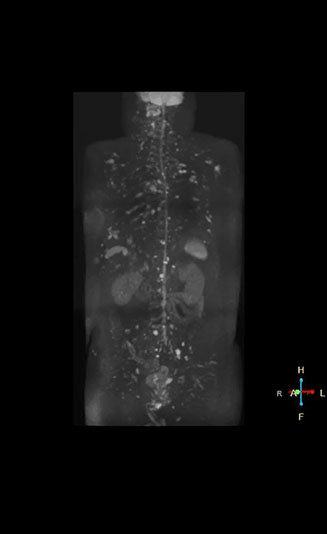

“When we limited the scan coverage to the area from neck to femur, we could fit more clinical information in approximately the same scan time. So, we added coronal mDIXON, sagittal T1-weighted, and sagittal STIR sequences to our examination, instead of performing only axial DWIBS and coronal single-shot TSE scans.” The single shot T2-weighted TSE images are used for morphology and compared to DWIBS images to identify T2 shine-through. Sagittal STIR images are used in patients with inflammation or bone metastasis.

“Switching to coronal DWIBS – rather than axial – further shortens scan time,” says Mr. Naka. “Important is that a dS SENSE factor of 5 shortens exam time while high image quality can be maintained, thanks to Ingenia’s dStream architecture.” He adds that the coronal orientation also avoids artifacts that are specific to combining axial images.

“When we use a coronal DWIBS acquisition, we can perform a full whole body examination, including other required sequences, within 30 minutes,” he says.